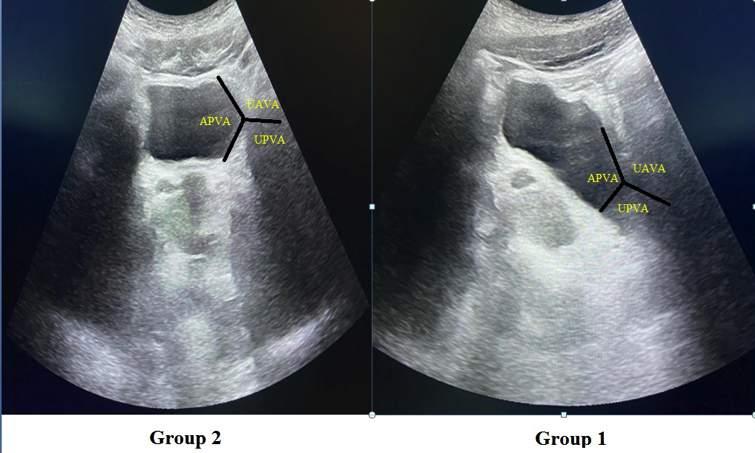

Issuu converts static files into: digital portfolios, online yearbooks, online catalogs, digital photo albums and more. Sign up and create your flipbook.